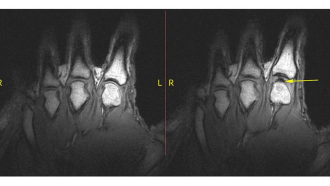

Stretching out your knuckles can sometimes release a sharp pop or two. Scientists have a new explanation for what’s behind the cracking.

Peterfactors/iStockphoto